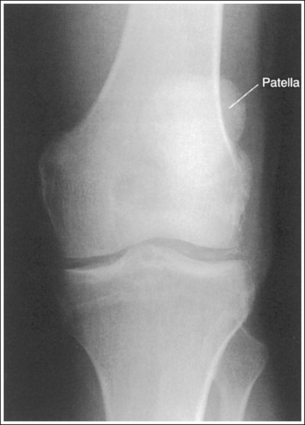

The knee demonstrates an AP projection. The medial and lateral femoral epicondyles are in profile, the femoral condyles are symmetrical, the intercondylar eminence is centered within the intercondylar fossa, and the tibia is superimposed over 0.25 inch (0.6 cm) of the fibular head.

• To obtain an AP knee projection, place the patient in a supine position with the knee fully extended. Internally rotate the leg until an imaginary line drawn between the medial and lateral femoral epicondyles is positioned parallel with the IR (Figure 6-71). This positioning places the medial and lateral femoral epicondyles at equal distances from the IR as well as medially and laterally in profile, respectively. It also centers the intercondylar eminence within the intercondylar fossa and draws the fibular neck and a portion of the fibular head from beneath the tibia.

The knee joint is at the center of the exposure field. One fourth of the distal femur and proximal lower leg and the surrounding knee soft tissue are included within the collimated field.

• Center the central ray to the midline of the knee at a level 1 inch (2.5 cm) distal to the palpable medial epicondyle to place the knee joint in the center of the exposure field. (As long as the knee remains extended, an alternative central ray placement is 0.5 inch (1.25 cm) distal to the patellar apex.) Open the longitudinal collimation enough to include one fourth of the distal femur and proximal lower leg. Transverse collimation should be to within 0.5 inch (1.25 cm) of the knee skin line.